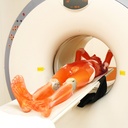

CT Whole Body Phantom - With Pathologies

1A unique, life size whole body phantom for CT provides a variety of educational application as well as visual evaluation in finding out optimal scanning conditions

| Training skills / Applications | Plain X-ray / CT /Basic patient positioning |